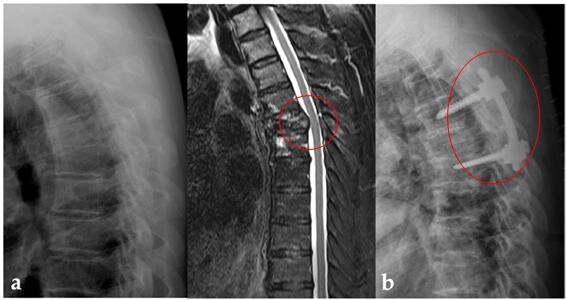

가톨릭대학교 서울성모병원 정형외과 김영훈 교수(교신저자)·은평성모병원 정형외과 박형열(제1저자) 교수팀은 ‘비소세포폐암 척추 전이 환자의 척추 수술과 방사선 치료 병합 요법 중요성’을 연구한 논문을 국제학술지에 게재했다.

2011년부터 2017년까지 비소세포폐암의 척추 전이로 척추 수술과 방사선 치료 병합 요법을 시행한 22명을 선정하였다. 이 후 환자를 나이, 성별, 기대 수명, 척추 불안정성을 고려한 1:1로 경향 점수 대응을 통해 방사선 단독 치료만 진행한 시행한 231명 중 비슷한 조건의 22명과 비교했다.

그 결과 방사선 단독 치료 군에서만 5명의 환자(22.7%)가 병적 골절로 인한 신경학적 증상의 악화가 관찰되었다. 또한 수술과 방사선 치료를 시행한 군에서는 보행이 불가능했던 4명의 환자가 보행이 가능하게 되었으며, 5명의 환자는 신경학적 증상이 개선됐다.

연구에 포함된 44명 환자의 생존율에 영향을 미치는 위험요인을 분석한 결과, 표적 항암제 치료가 가능한 돌연변이 여부와 신체 활동 정도가 생존율과 의미있게 관련이 있는 것으로 밝혀졌다. 특히 평균 생존율을 비교한 결과, 표적 항암제 치료가 가능했던 환자 군은 21개월인 반면, 고식적인 항암제로 치료한 환자 군은 5개월로 매우 짧은 것으로 나타났다.

김영훈 교수는 “비소세포폐암이 척추로 전이된 환자는 임상적으로 흔하지만 치료방법을 결정하기 쉽지가 않은데, 수술적 치료가 병적 골절 예방을 통해 장기적으로 신경학적 증상의 악화를 막을 뿐만 아니라, 신경학적 결손이 발생한 환자에서 직접적인 신경 감압을 통해 보행과 신경학적 증상을 호전시키는 효과를 보인다는 것을 이번연구로 확인하였다”고 설명하였다.